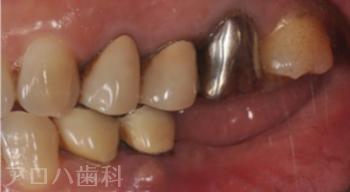

CASE01/50代男性

初診時

治療終了後5年時

| 主訴 | 左の奥歯が噛めない |

|---|---|

| 治療内容 | 下顎臼歯3歯欠損をインプラントで修復しました。 デジタル機器を使いコンピュータで理想的な歯の形態を設計。 歯ぐきに隙間が出来る事なく修復できました。 |

| 治療期間 | 3ヶ月 |

| 治療費用 | 1,375,000円 |

| 費用詳細 | ・サージカルガイド 55,000円 ・GBR 110,000円 ・インプラント手術+アバットメント+上部構造(3歯) 1,320,000円 |